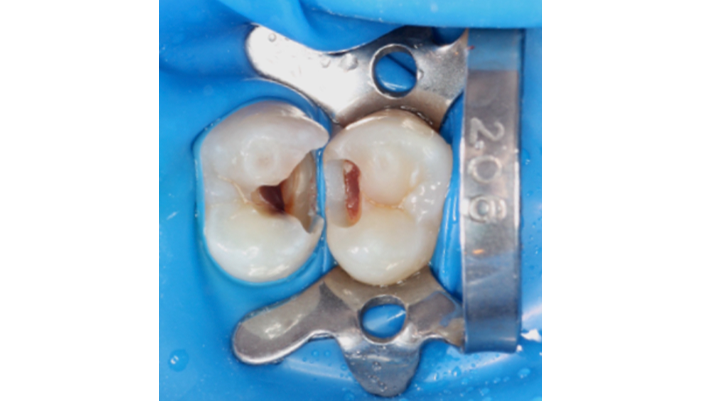

症例1

治療前

治療中

患者様は「他院で神経を取るしかないと言われたが、できれば神経を残したい」とのご希望で来院されました。初診時には冷たいものがしみる症状はありましたが、自発痛や打診痛はなく、診査の結果、歯髄を温存できる可能性があると判断しました。

治療では拡大視野下でむし歯の感染部分を正確に除去し、MTAを用いた歯髄温存療法を実施しました。

| 主訴 | 歯に穴が空いた |

|---|---|

| 治療期間 | 1ヶ月 |

| 治療費 | ¥33,000 |

| 治療内容 | むし歯が大きく、神経を残す治療(歯髄温存療法)を行い、神経を残しダイレクトボンディングにて修復しました。 |

| 治療のリスク | 治療後に痛みが出ることがあります。また、痛みが強くでる場合は神経を取る治療に移行することもあります。 |